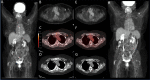

Background: mRNA COVID-19 vaccines are known to provide an immune response seen on FDG PET studies. However, the time course of this metabolic response is unknown. We here present a temporal metabolic response to mRNA COVID-19 vaccination in oncology patients undergoing standard of care FDG PET.

Methods: 262 oncology patients undergoing standard of care FDG PET were included in the analysis. 231 patients had at least one dose of mRNA COVID-19 vaccine while 31 patients had not been vaccinated. The SUVmax of the lymph nodes ipsilateral to the vaccination was compared to the contralateral to obtain an absolute change in SUVmax (ΔSUVmax).

Results: ΔSUVmax was more significant at shorter times between FDG PET imaging and COVID-19 mRNA vaccination, with a median ΔSUVmax of 2.6 (0-7 days), 0.8 (8-14 days), and 0.3 (> 14 days), respectively.